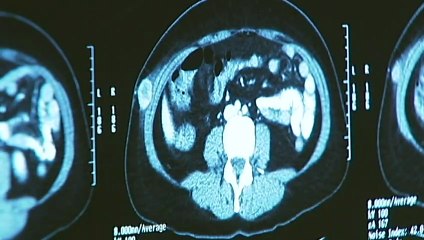

Scientists render the virus 'infertile' so it can't infect people once injected.